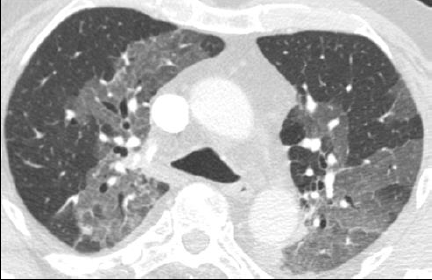

Verre dépoli

GHAYE B. - 2021 - UCL

Cardio-thoracique DES SPECIALITE